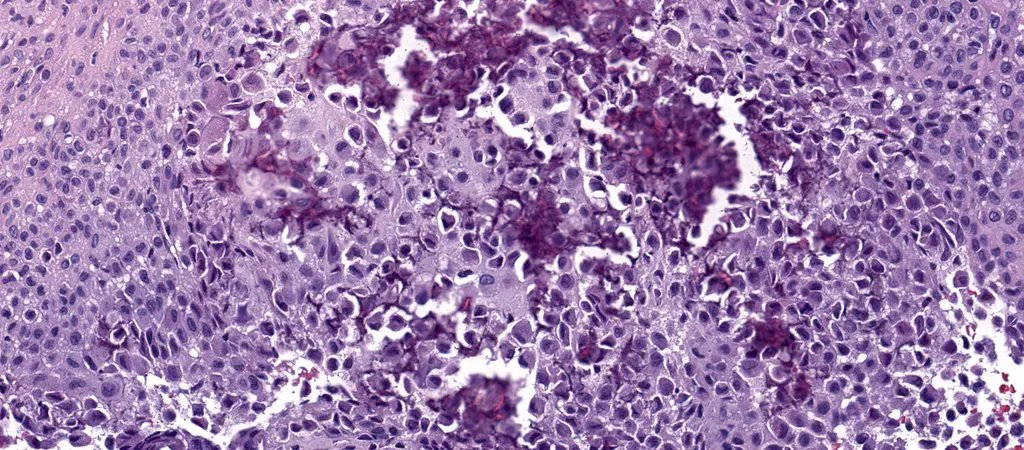

Microscopic (histologic) description

- Composed of round or polyhedral chondroblasts with abundant eosinophilic cytoplasm and well defined cell borders; spindle shaped cells may be focal (Ann Diagn Pathol 2003;7:205, Cancer 1972;30:401)

- Nuclei are oval, hyperlobulated with grooves

- Pericellular lace-like or chicken wire type calcification among degenerative chondroblasts

- Chondroid matrix almost always present (pink rather than blue matrix)

- May have marked cellularity, intracytoplasmic glycogen granules, mitotic figures, necrosis and osteoclast type giant cells

- No significant nuclear atypia as compared with malignant chondroblastoma (Mod Pathol 2020;33:2295)

- Aneurysmal bone cyst-like change is common (Skeletal Radiol 2010;39:583)

Microscopic (histologic) images

An 18 year old man presents with a 3 cm, well defined lucent lesion within the epiphysis of the distal femur. Microscopic features of the surgical curettage specimen are represented by the H&E images. The best diagnosis is

A. Chondroblastoma. Chondroblastomas commonly present in the second decade of life as a singular, well defined lucent lesion within skeletally immature long bones. Characteristic histopathological features include sheets of chondroblasts admixed with osteoclast-like giant cells in a chondroid matrix and focal chicken wire type calcification. Chondroid fibromas typically lack chicken wire type calcification. Chondroblastoma-like osteosarcomas generally display an infiltrative growth pattern with marked cytologic atypia. Chondroid matrix is not commonly seen in giant cell tumor of bone.